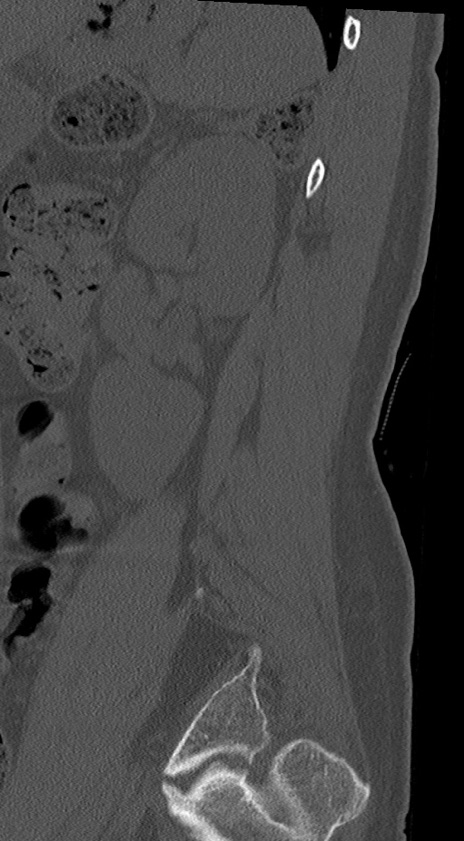

腰椎CT

冠状断像